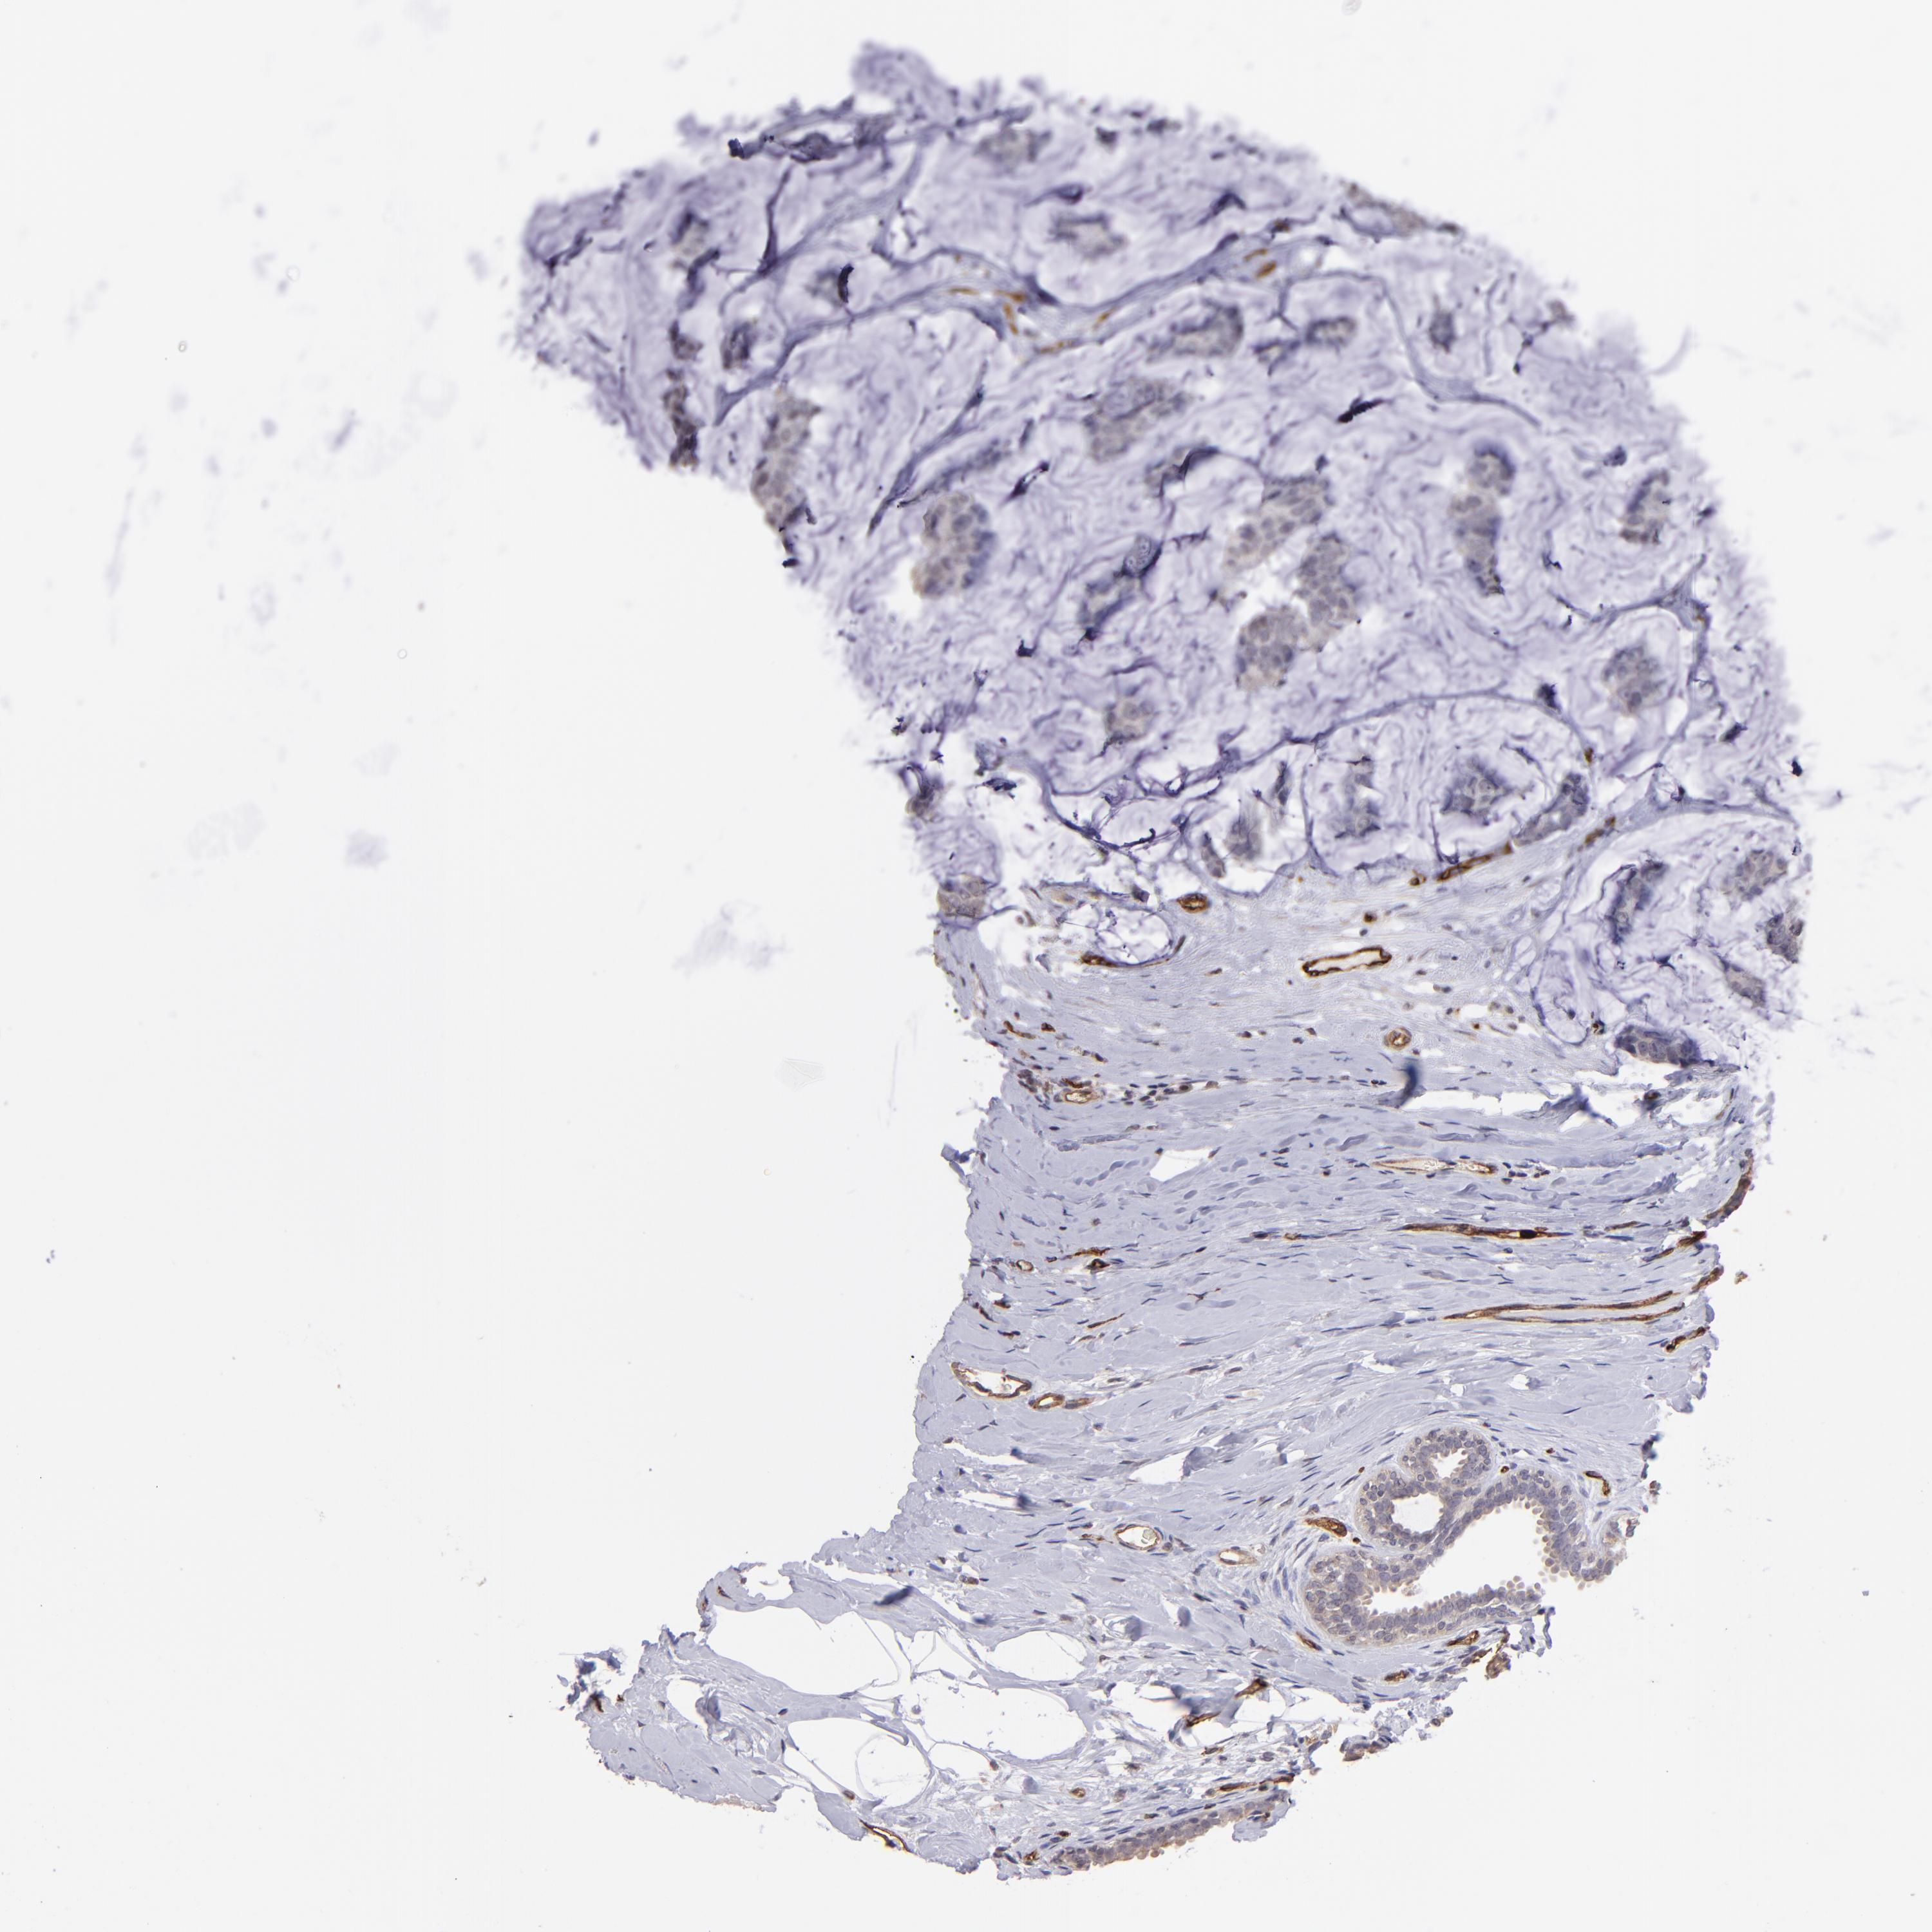

CANCER BREAST CANCER Show tissue menu

BRCA TCGA BRCA VALIDATION PROTEIN EXPRESSION